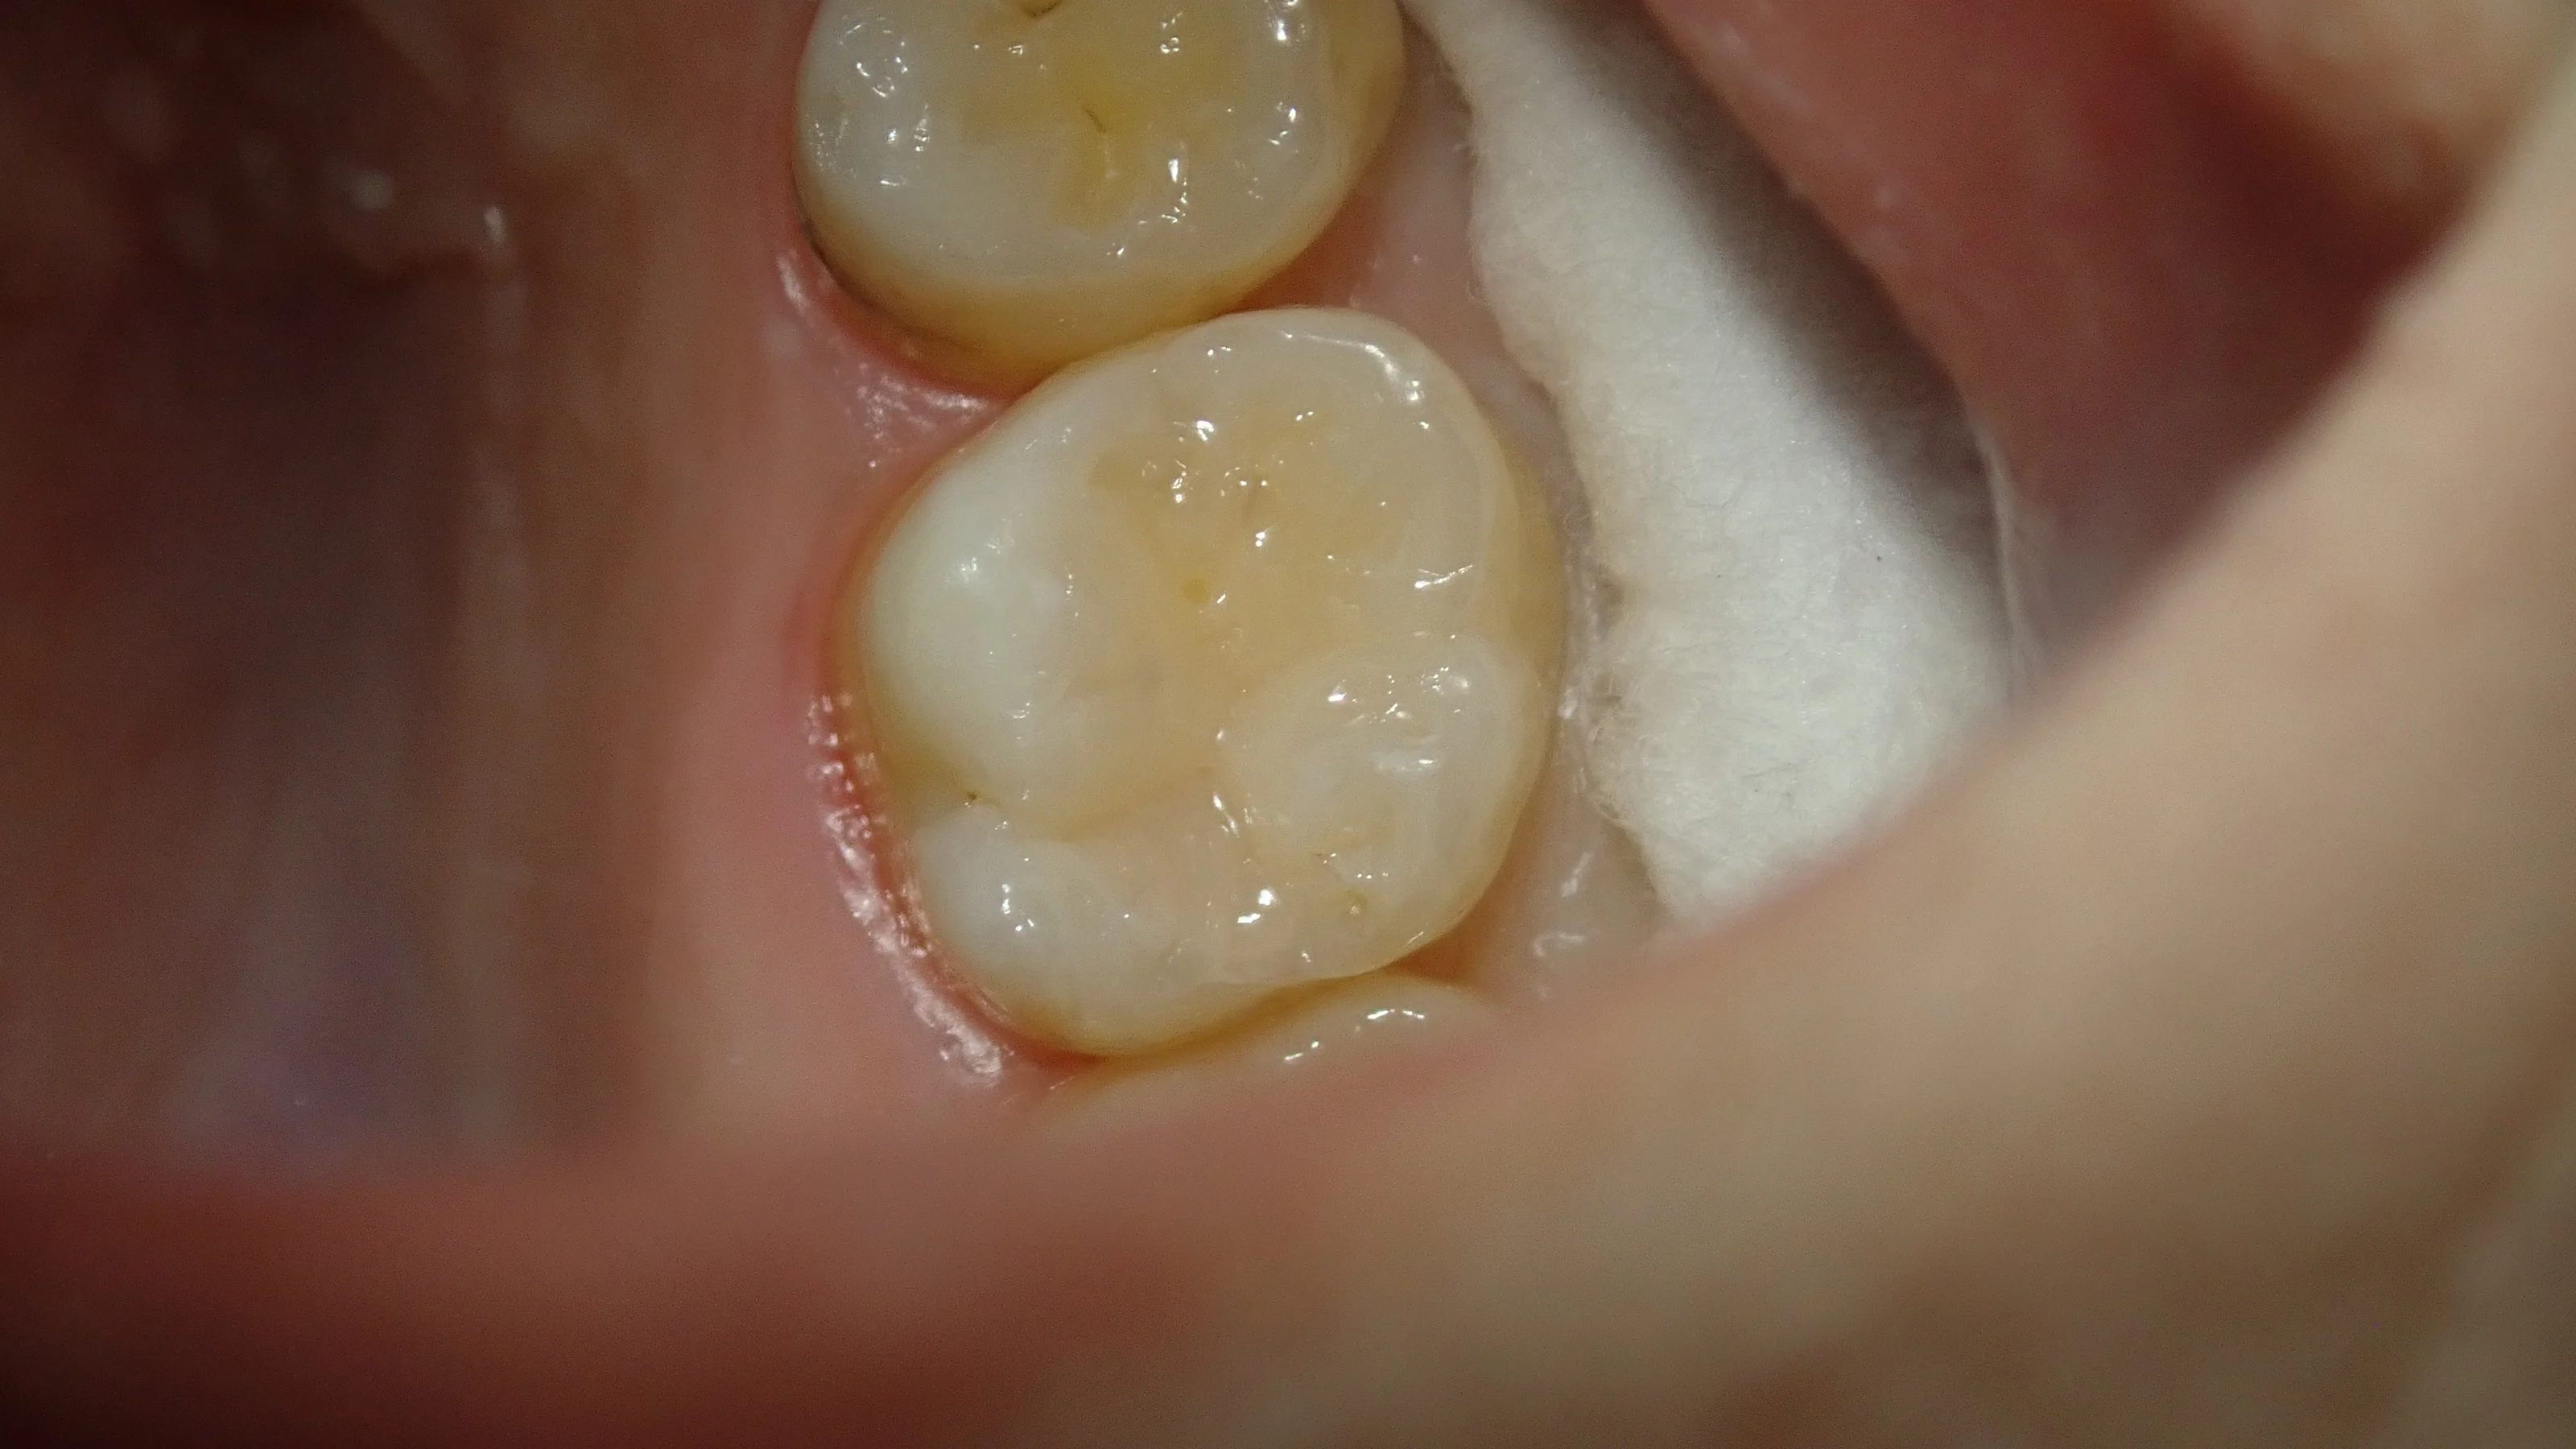

術後が、こちらです。

ダイレクトボンディングの技術の向上により、コンポジットレジン充填でもかみ合わせの調整が殆ど不要になってきました。

まぁ、ステインとかは入れていないので、歯科医師や歯科衛生士が診れば直ぐにどこを治療したのかわかっちゃいますけどね(;'∀')

恒例の術前術後がこちらです。

術後、染みも無くなり、噛んだ時の違和感も消えたそうで、ホッとしました。